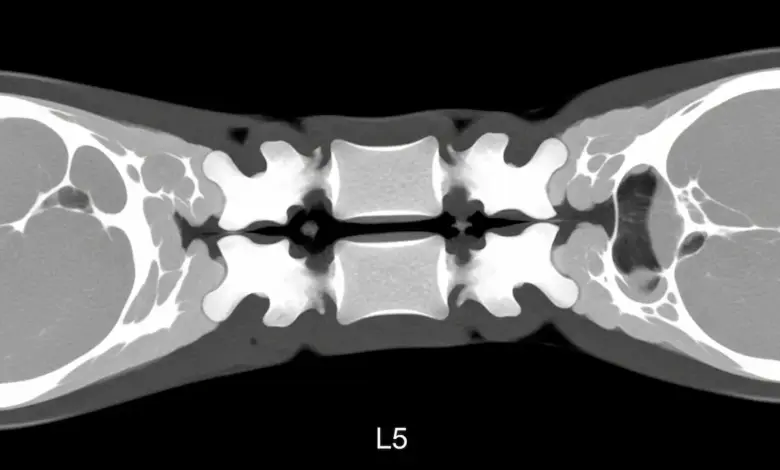

- A tomografia confirma a linha de fratura.

Ocorre com maior frequência em L5 e L4, costuma surgir por microtraumas repetidos e pode aparecer sem sintomas. De acordo com a estudo publicado no PubMed.